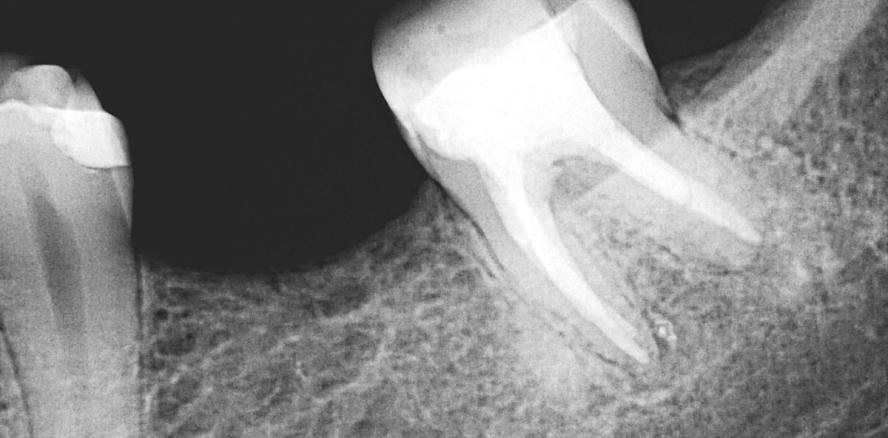

Eine 33-jährige Patientin wird zur Revision von Zahn 37 überwiesen. Im OPTG der überweisenden Kollegin (Abb. 1) zeigt sich eine ausgedehnte apikale Parodontitis und eine unvollständige Wurzelfüllung an diesem Zahn (sowie an Zahn 16, 26 und 46). Die Sondierungstiefe bei Zahn 37 beträgt 2–3 mm, der Lockerungsgrad 0–1, der Zahn ist weder perkussions- noch druckempfindlich.

Nach einem aktuellen präoperativen Einzelröntgenbild (Abb. 2) wird zunächst ein adhäsiver präendodontischer Aufbau aus Komposit erstellt. Nach der Trepanation zeigt sich unter dem Operationsmikroskop ein infiziertes Kanalsystem mit nicht randständiger Wurzelfüllung (Abb. 3). Die mikro­biell besiedelte Guttapercha lässt sich aus dem distalen Kanal mit einer Mikrozange widerstandslos herausziehen (Abb. 4). Nach sonoabrasiver Beseitigung einiger kleiner Dentikel und der Entfernung der alten Wurzelfüllmasse aus den mesialen Kanälen wird die Arbeitslänge endometrisch bestimmt und röntgenologisch bestätigt (Abb. 5). Es folgt die initiale Präparation mit manuellen und rotierenden NiTi-Instrumenten sowie eine Calciumhydroxid-Einlage samt adhäsivem, provisorischem Verschluss aus Komposit.